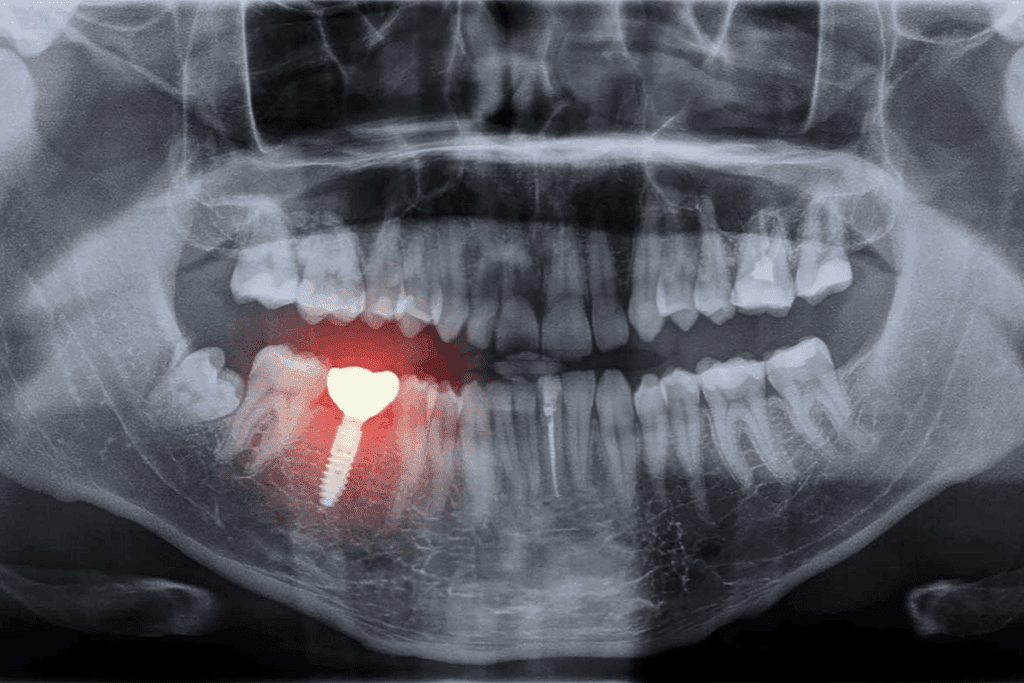

Clinical Applications of Panoramic Dental X-Rays

Panoramic dental X-rays are key in today’s dentistry. They help in planning treatments by showing the whole mouth. This is because they give a full view of the oral cavity.

Orthodontic Assessment and Planning

For orthodontics, panoramic X-rays are very helpful. They show the teeth’s position and any hidden teeth. This helps orthodontists plan the best treatment for their patients.

Wisdom Teeth and Impaction Evaluation

These X-rays are also great for checking wisdom teeth. They show the back of the mouth clearly. This helps dentists decide if wisdom teeth need to be removed and how to do it.

Conditions Detected Through Panoramic Imaging

Panoramic dental X-rays have changed how we diagnose dental problems. They show us things we can’t see with our eyes. These images give a full view of the mouth, including teeth, jaws, and more. This helps us find many conditions that might go unnoticed.

Panoramic X-rays are great for finding hidden dental issues. They help spot impacted wisdom teeth, early cavities, fractures, and bone loss. They also find developmental problems like supernumerary teeth or odontomas.

Seeing the whole dental arch in one image lets us check dental health. This early check can help prevent bigger problems later.